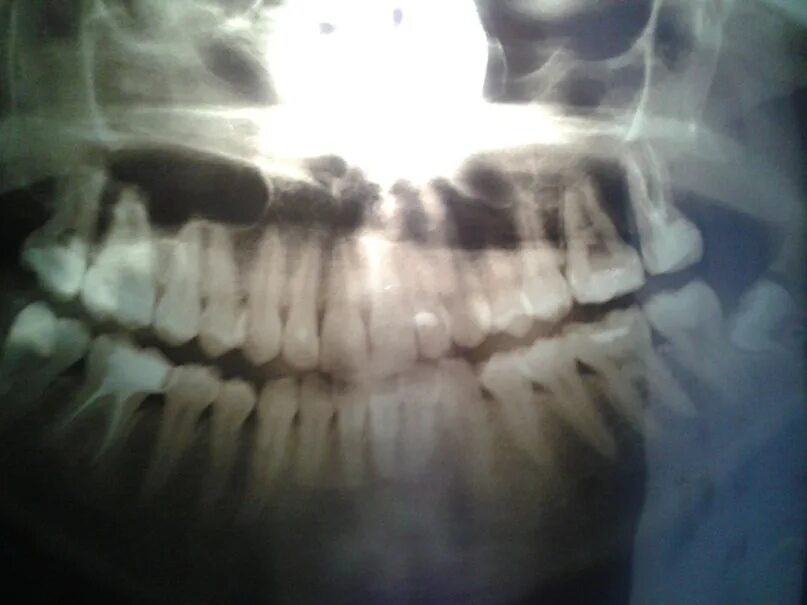

Трясет челюстью